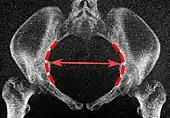

Obstetric conjugate

Median plane, 20 mm thick

Same, but may require minor side-to-side scrolling to visualize both end points. The line between the closest bony points of the sacral promontory and the pubic bone next to the symphysis 10 to 12 cm.[4]